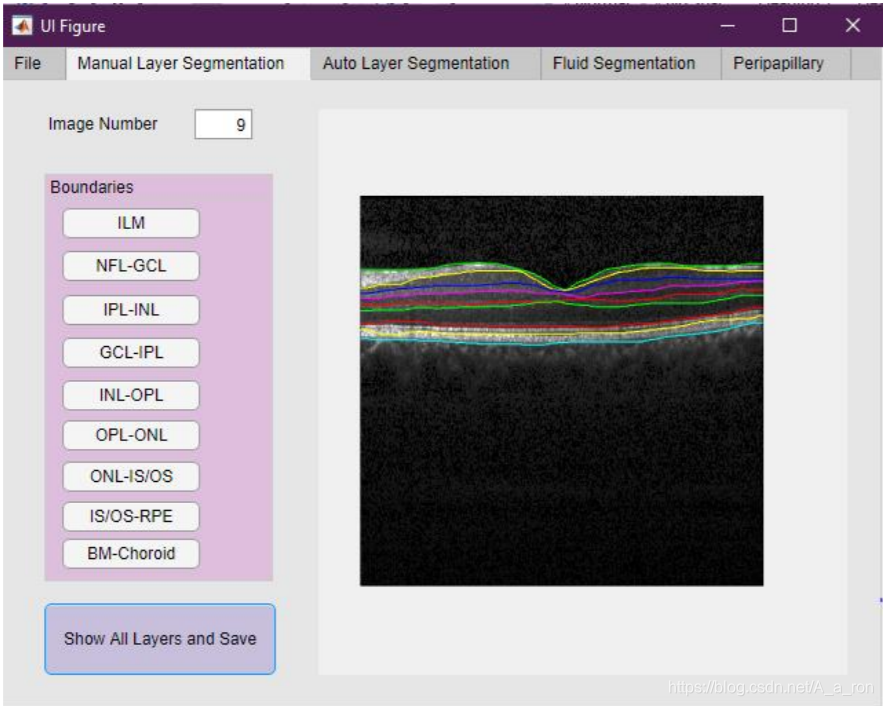

5. Livelayer

Livelayer: A Semi-Automatic Software for Segmentation of Layers and Objects in Optical Coherence Tomography Images,一个基于Matlab的半自动的视网膜层次分割软件。目前该论文仅仅发在Arxiv上(2020年3月份),没有提供网站介绍和下载链接。论文中给出的界面如下:

手动分割界面: